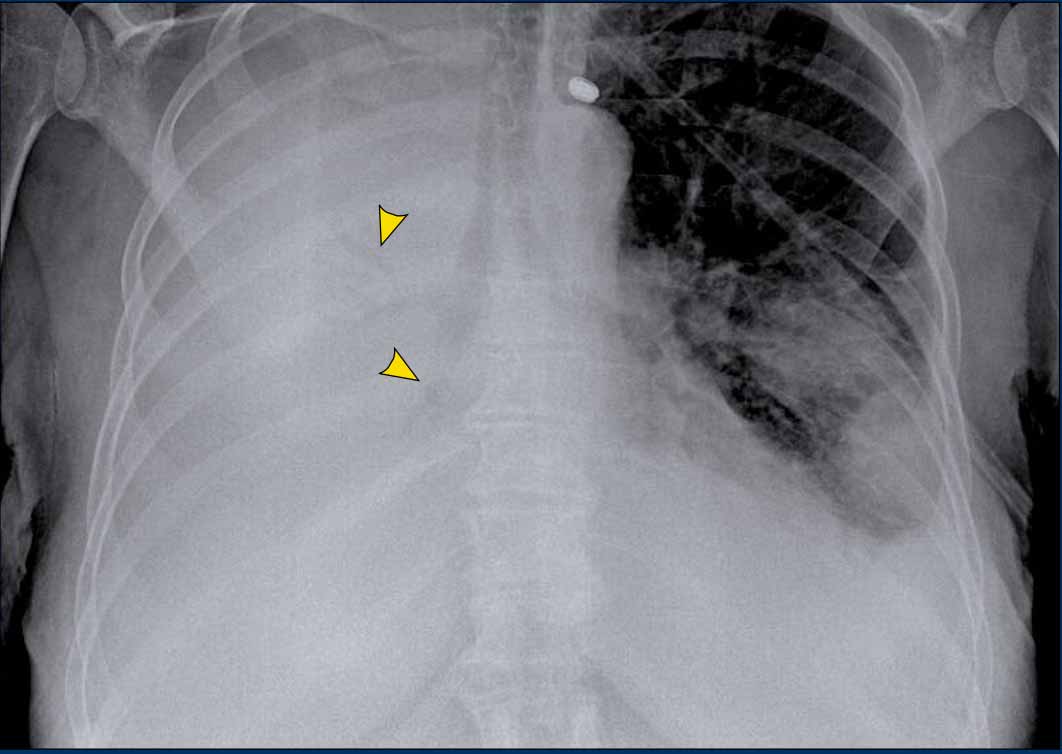

Case Example

A patient with bilateral carcinomatous pleuritis.

Findings

- Complete opacification of the right hemithorax.

- Air bronchogram in the right main bronchi (arrowheads), indicating compression atelectasis of the lung due to massive effusion.